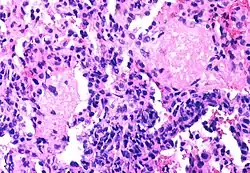

Pneumocystis jiroveci pneumonia

The diseases associated with AIDS, such as Pneumocystis jiroveci pneumonia (PCP) and Mycobacterium avium complex (MAC), are not caused by HIV, but rather result from the immunosuppression caused by HIV disease. As the immune system of an HIV-infected individual weakens, he or she becomes susceptible to the particular viral, fungal, and bacterial infections common in the community. For example, HIV-infected people in the Midwestern United States are much more likely than people in New York City to develop histoplasmosis, which is caused by a fungus. A person in Africa is exposed to pathogens different from individuals in an American city. Children may be exposed to different infectious agents compared to adults.[87]